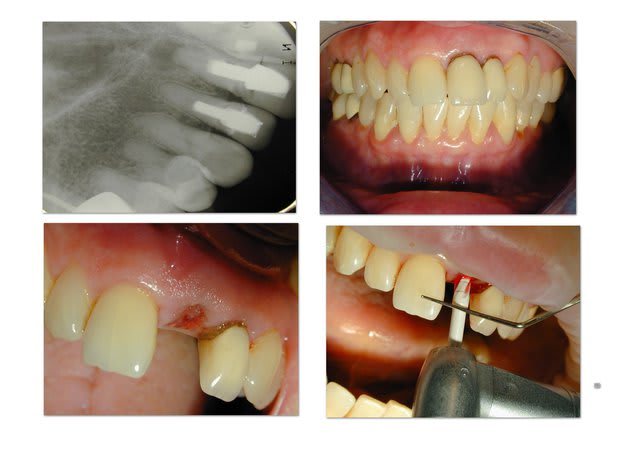

Voila: extraction curetage, implantation à 1 semaine, tranquille.

Le col de la prov est volontairement un peu étroit pour éventuellement faire un "Bichacho" plus tard.

Rom1 wmgjgx - Eugenol

Rom2 yakwup - Eugenol

Rom j14 hiy9ln - Eugenol

Longueur =16. Je n'avais pas de scan, mais j'avais la racine, elle fait 10, 3mm de granulome, il faut plus long si on aime les implants "minces" (ça c'est un autre débat)